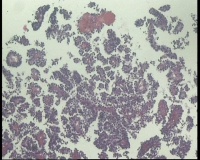

| 一般病史 | 彩超:盆腔可见囊实性回声,囊性为主,大小约5.0x3.7厘米,其内可见分隔回声,部分分隔内回声不纯净,形态欠规整 | ||||

| 标本名称 | 腔镜下右侧卵巢囊肿手术 | ||||

| 大体所见 | 囊壁样组织5.5x5.0厘米,4.5x2.5厘米2块,壁厚0.1-0.2lm,囊壁大部分光滑,局灶见0.7x0.5x0.3厘米淡黄色突起组织,另见淡黄色、肉粉色质软组织2.8厘米一堆。 | ||||